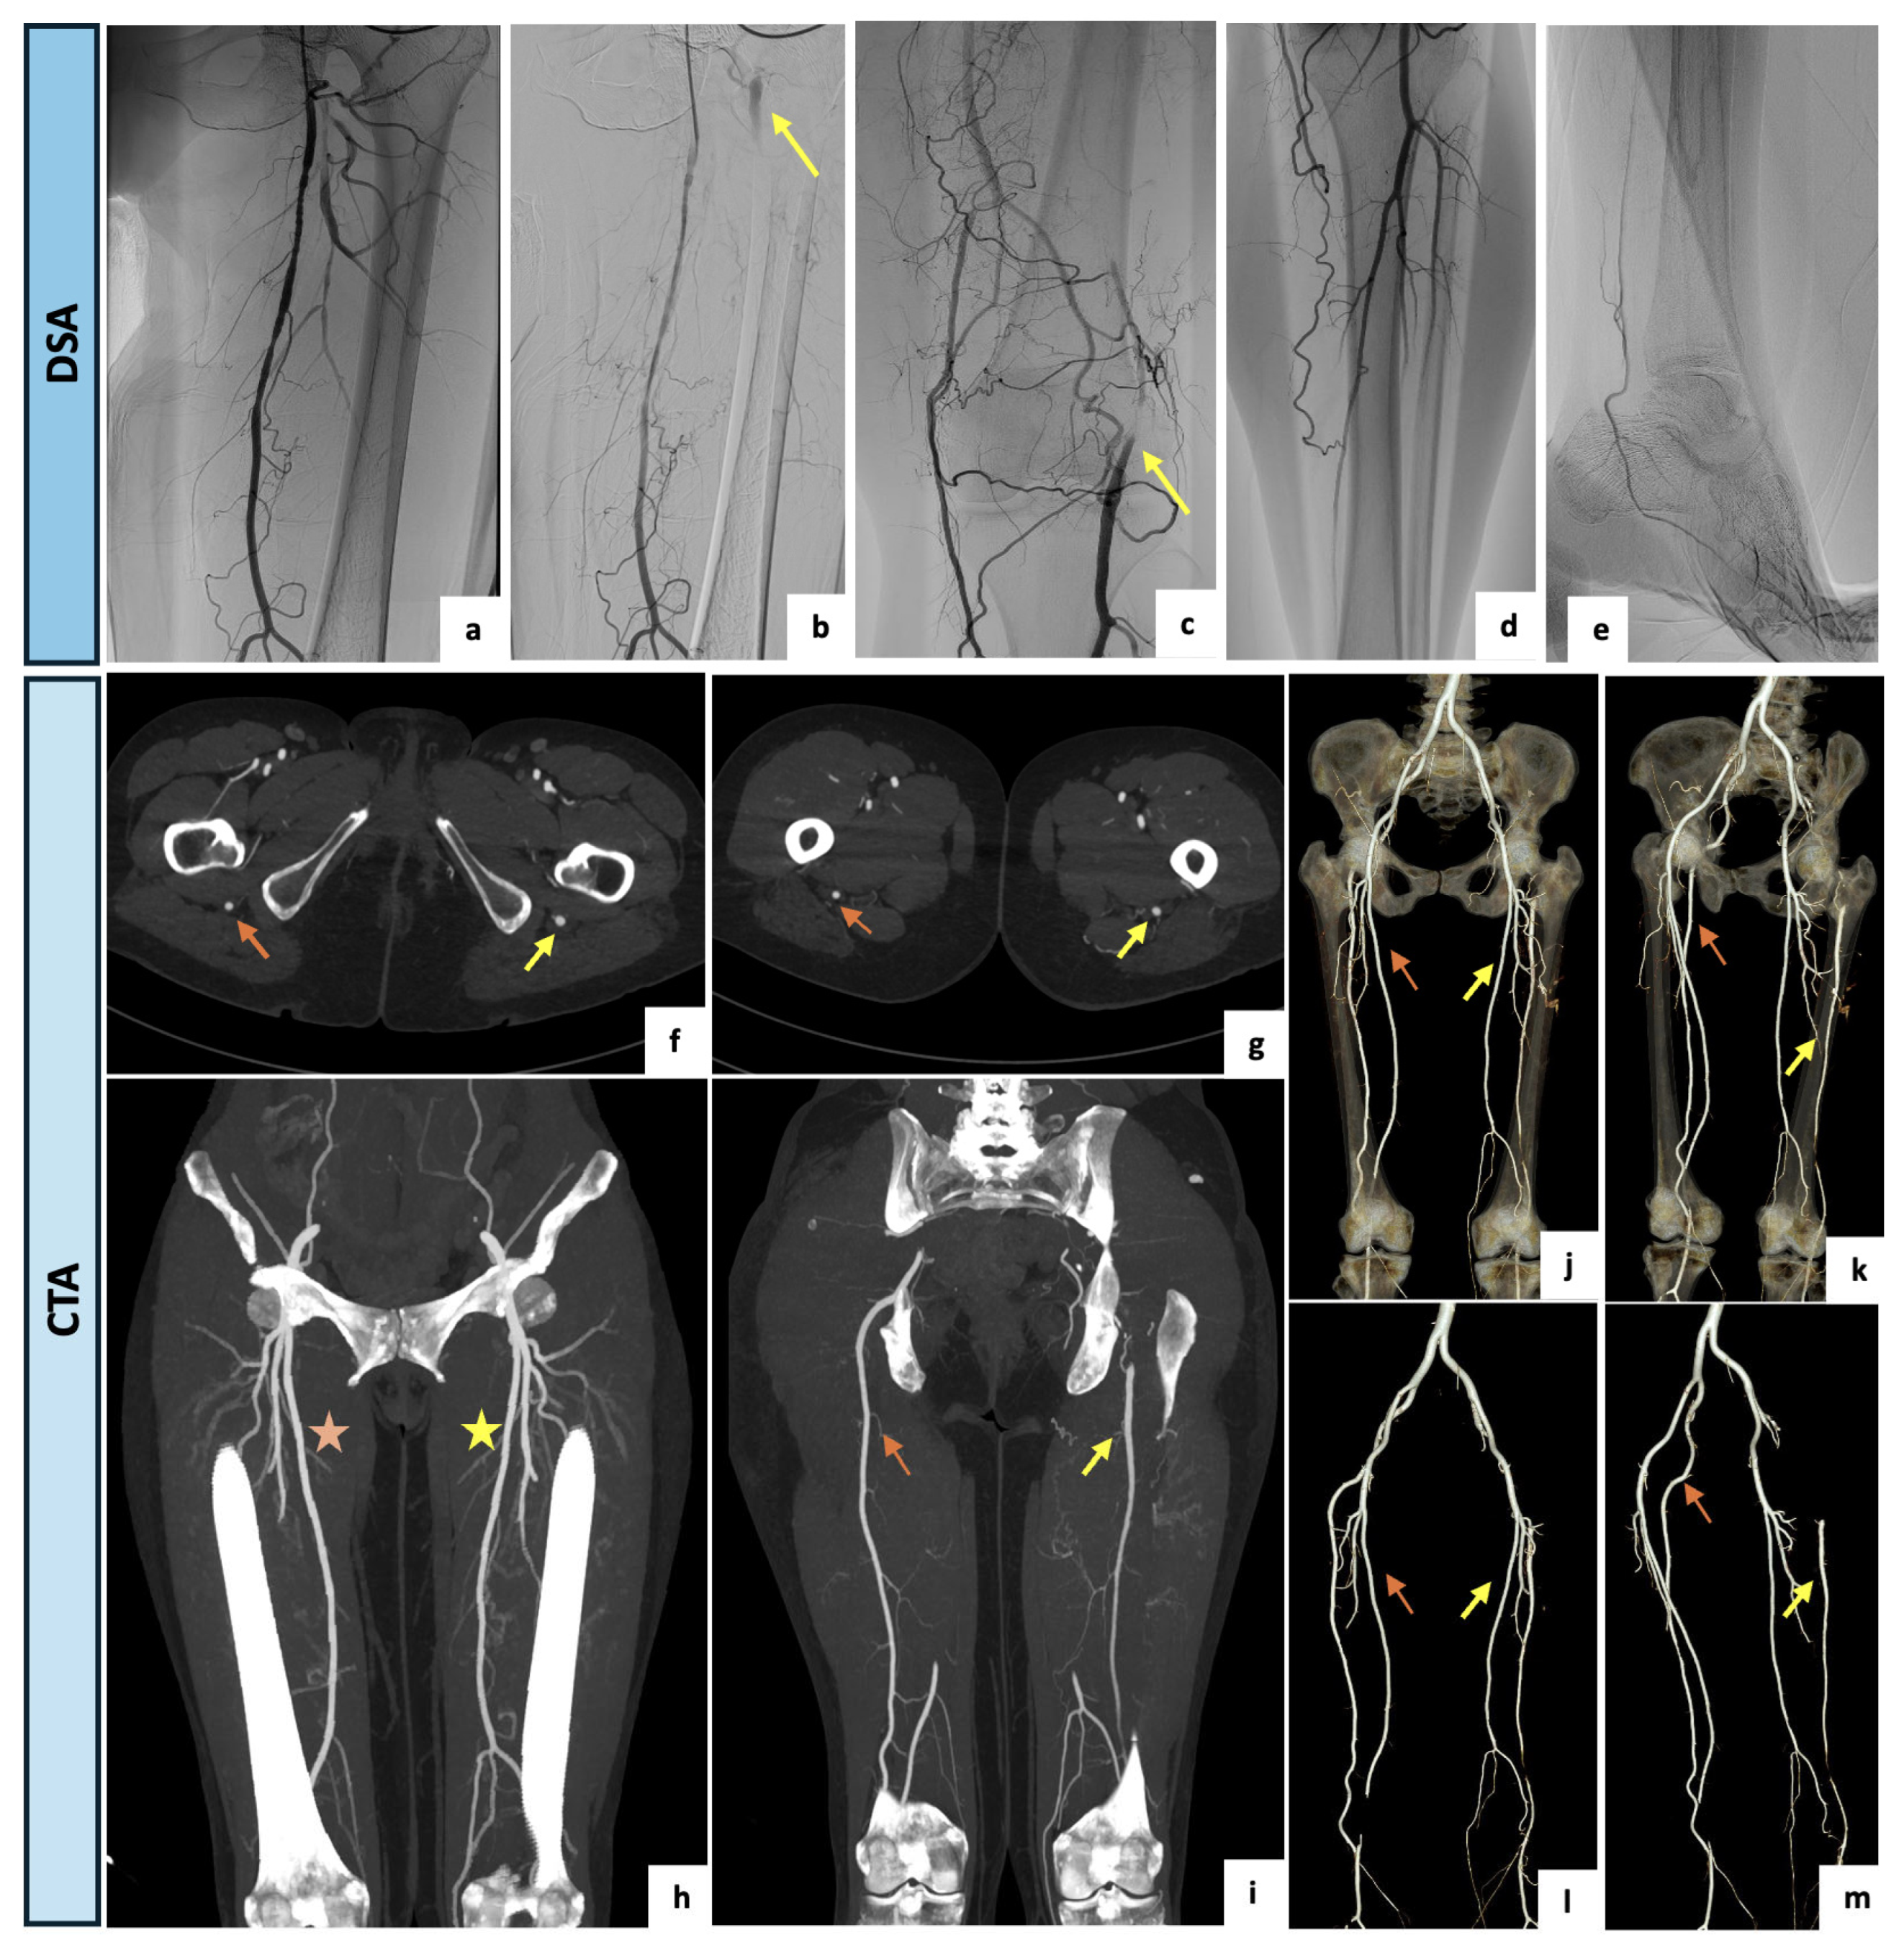

| 4 | 61 | Female | Type IIb bilateral claudication with left side worsening | CTA | Right limb: Type 1 Left limb: Type 2a | Medical management: smoke cessation, exercise training, glucose-lowering therapy, anti-platelet agents and cilostazol. | Clinical FU: progressive improvement. |